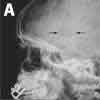

X-ray films of the skull showed a circular defect and an overlying soft tissue swelling (A). CT scans of the head confirmed the solitary bone defect in the skull without any involvement of the brain (B). The complete blood cell count was within normal limits.